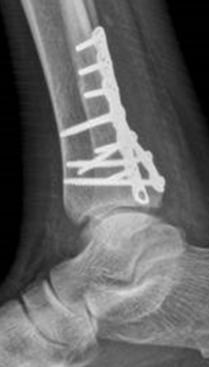

Ankle fractures- otherwise known as broken ankles are common injuries in people of all ages and lifestyles. They may occur during any sport involving a twisting or jumping motion such as football, basketball, ballet, and running. They may also occur as a result of a motor vehicle accident, slip or fall from a height. People (particularly post-menopausal women) with osteoporosis may be susceptible. When one breaks an ankle, they have fractured one or more of three bones which make up the ankle. If treated improperly the injury could lead to long-term disability. The ankle joint is made up of the tibia (shin bone) the larger of two bones in the lower leg and flares out at its lower end forming a knob on the inside of the ankle called the medial malleolus and another flare in the back known as the posterior malleolus. The smaller of the two bones in the leg is the fibula and flares out on the outside of the ankle to form the lateral malleolus. The tibia and fibula rest on the talus, a wedge-shaped bone connecting the foot to the leg. We think of the ankle as a room with three sides and a roof. The tibia forms the roof, the medial malleolus (inside wall), and the posterior malleolus (backside wall). The lateral malleolus forms the outside wall of the room. Ligaments connect these structures together to guide movement and assure stability. If a major ligament such as the Deltoid or Syndesmotic ligament is torn the ankle is generally considered unstable. A syndesmotic tear may involve a fracture of the fibula near the knee (Maisonneuve fracture). The lateral malleolar ankle fracture is the most common, and bimalleolar (lateral and medial) the second most common. When all three sides are fractured (medial, lateral, and posterior) the injury is referred to as a trimalleolar fracture. As the number of fractures or level of impact increases so does the risk of long-term damage to the ankle joint. Ankle fractures may be nondisplaced (in correct position) or displaced (misaligned). High velocity fractures are known as Pilon fractures and have the worst long-term prognosis because of the extensive comminution and damage to the joint. These fractures inherently pose the worst long-term prognosis reduction using specialized plates and because the ankle shatters in many pieces screws. A foot and ankle specialist may wait and quite often lead to chronic disability and one to three weeks for swelling to resolve arthritis regardless of how well the ankle before the ankle is surgically repaired. After was repaired. Many of these patients will surgery, patients must remain non-weight inevitably require additional surgery in the bearing for a period of anywhere from future to eliminate pain. The procedures 4-6 weeks to a few months depending on may include fusion where the bones are the severity of the fracture. A graduated welded together or an ankle replacement. rehabilitative period is prescribed during the

X-rays of the ankle and knee are postoperative period to allow the patient required to diagnose an ankle fracture. to regain movement, strength, and balance. More advanced imaging such as CT or Risk factors for poorer outcomes in proper MRI is often necessary to determine the healing of ankle fractures include smoking, extent of the injury. With modern imaging diabetes (especially if under poor control), techniques, a three-dimensional recreation age, and peripheral neuropathy. of the fracture can be obtained with a CT scan allowing the surgeon to fully assess the fracture. Treatment is based on the alignment and stability of the ankle with the goal being to heal the fracture(s) as close to ⊲ Dr. Cohen is a published author, is on faculty at several South Florida residency programs, podiatric medical colleges and frequent lecturer. He practices with the Foot, Ankle and Leg Specialists of South Florida specializing in lower perfect as possible. A fracture displaced 2 leg injuries and reconstructive surgery of the or more millimeters can result in long term foot and ankle. The practice includes Robert problems and often necessitates an operation. Unfortunately, arthritis may develop even when the ankle has been placed in good alignment because of the irreparable damage done to the bone and cartilage at Sheinberg DPM, Al DeSimone MD, Fernando Moya MD PhD, Alexander Bertot MD, David Shenassa MD, Carlo Messina DPM, Franz Jones DO and John Goodner DPM. The South Florida Institute of Sports Medicine in Weston is located at 1600 Town Center Blvd., Suite C, (954) 389the time of injury. Not all fractures require 5900 and in Pembroke Pines at 17842 NW 2nd surgery. Simple nondisplaced fractures may be treated with a cast or walking boot. More Street, (954) 430-9901 The practice website is www southfloridasportsmedicine.com severe injuries however require surgical